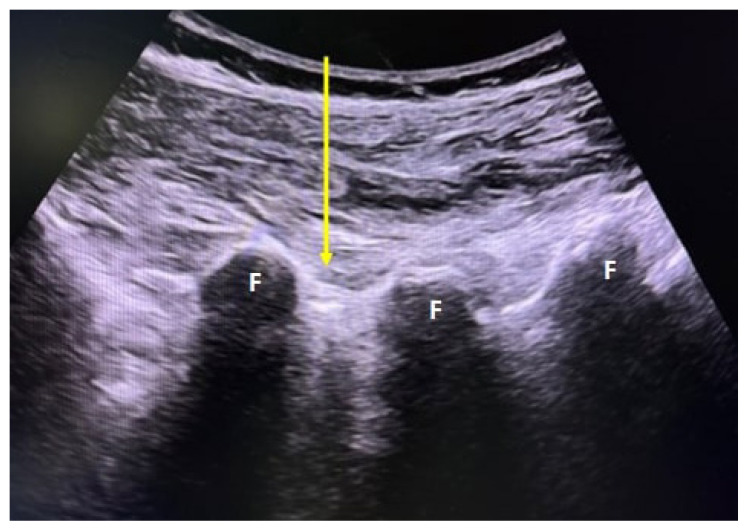

Materials and methods: A total of 50 patients were randomly divided into 2 groups of 25 patients each underwent PFOI by USG or TFESI via fluoroscopy. Pain intensity was assessed with visual analogue score (VAS), disability with Oswestry disability index (ODI), and QoL with short form-36 (SF-36), before treatment, at the 2nd week, 1st month, and 2nd month, after treatment.

Abstract Image